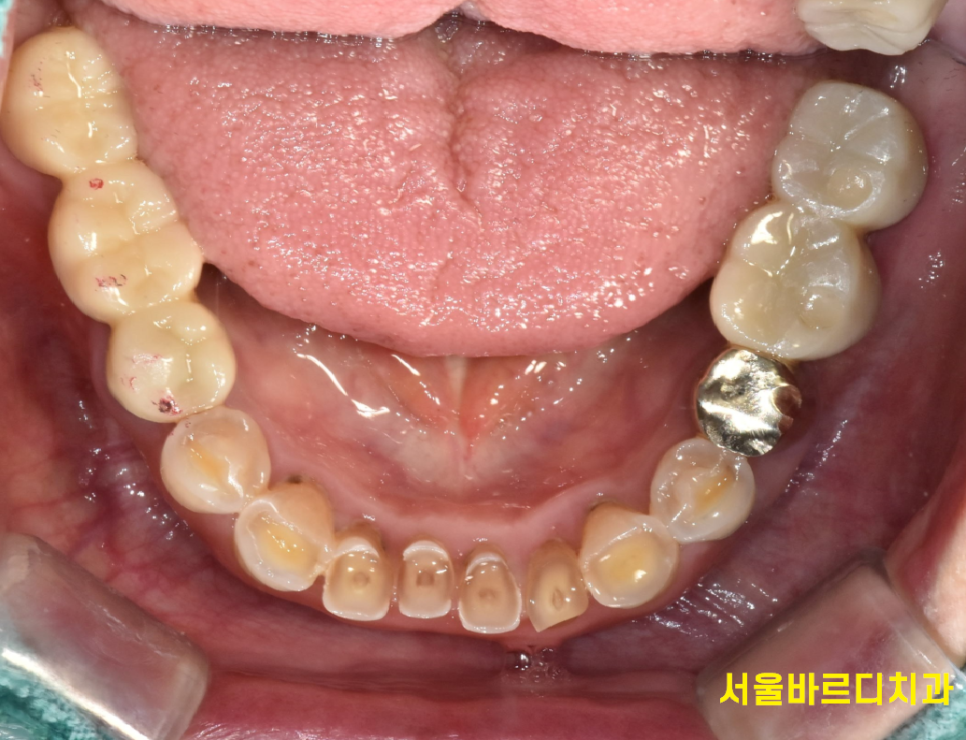

목이 부러져서 건들거리는 왼쪽 아래가

제일 불편하다고 하셔서

위 아래 임플란트를 왼쪽부터 1차 진행

한달 뒤 오른쪽 임플란트 수술을 진행했습니다.

230829

오른쪽 수술을 마친 직후입니다.

240202

딱 5번 내원하셔서 치료를 끝내드렸습니다.

24.2.2

이가없던 위 어금니도

문제가 있던 아래 어금니도

문제가 있는 부분 싹 고쳐드렸습니다.